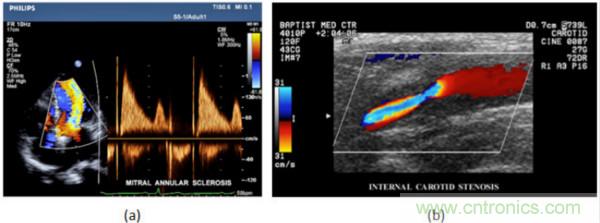

在CW和PW多普勒模式中,流信息是從一個聚焦聲束中獲得的,類似于A模式成像。在20世紀80年代,研究人員基于彩色多普勒技術完成了血流分布的二維信息可視化。彩色多普勒處理也是基于B模式/PW模式信號路徑。從感興趣區(qū)域收集多幀RF數(shù)據(jù)。由于感興趣區(qū)域中的血液流動導致圖像幀之間存在數(shù)據(jù)差異。相域中的自相關和時域中的互相關兩種算法可從RF數(shù)據(jù)中提取數(shù)據(jù)方差(即血流速度和方向信息):。根據(jù)預定義的顏色漸變條相應地映射包括速度和方向的血流信息。通常,藍色和紅色代碼分別識別朝向和遠離換能器移動的血流。當流速增加時使用更亮的顏色,反之亦然。顏色映射的2D分布始終疊加在B模式圖像上,以實時同時顯示個體解剖結構和血流。它對于診斷心血管疾病,如血管閉塞和心臟瓣膜反流,極其有用。典型的彩色多普勒圖像如下圖所示,(b)顯示頸動脈狹窄引起的血流流速變化。

圖7.彩色多普勒成像:(a)以彩色多普勒和CW模式獲得的圖像(由Philips提供); (b)顯示頸動脈狹窄的彩色多普勒(由GE提供)